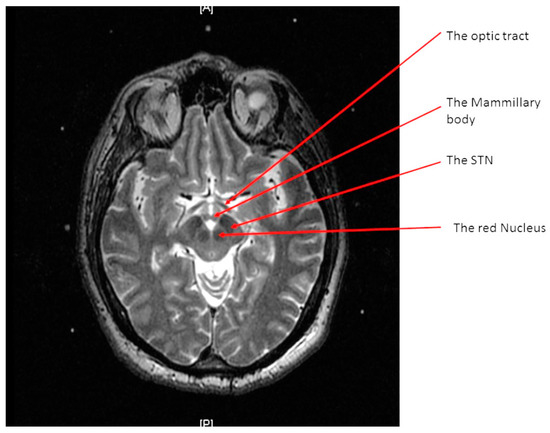

The STN is a small gray matter structure located at the junction of the midbrain and diencephalon. It has anatomic relationships to the internal capsule and the Globus Pallidus Internus (GPi) anterolaterally, the Zona Incerta (ZI) and the thalamus superiorly, fibers of the third nerve anteromedially, the red nucleus (RN) posteromedially, and the cerebral peduncle and the Substantia Nigra (SN) ventrally [2,3]. The target of DBS is the sensorimotor (dorsolateral) part of the STN [4,5]. This complex anatomy of the STN necessitates precise targeting during DBS surgeries.

The STN is the hypointense structure located lateral and anterior to the red nucleus on axial T2 MRI (Figure 4) [8]. The center of the STN hypointensity was identified at the extension of a straight line drawn at the anterior margin of the RN bisecting the STN. Then, the coordinates were calculated using the same Excel worksheet.